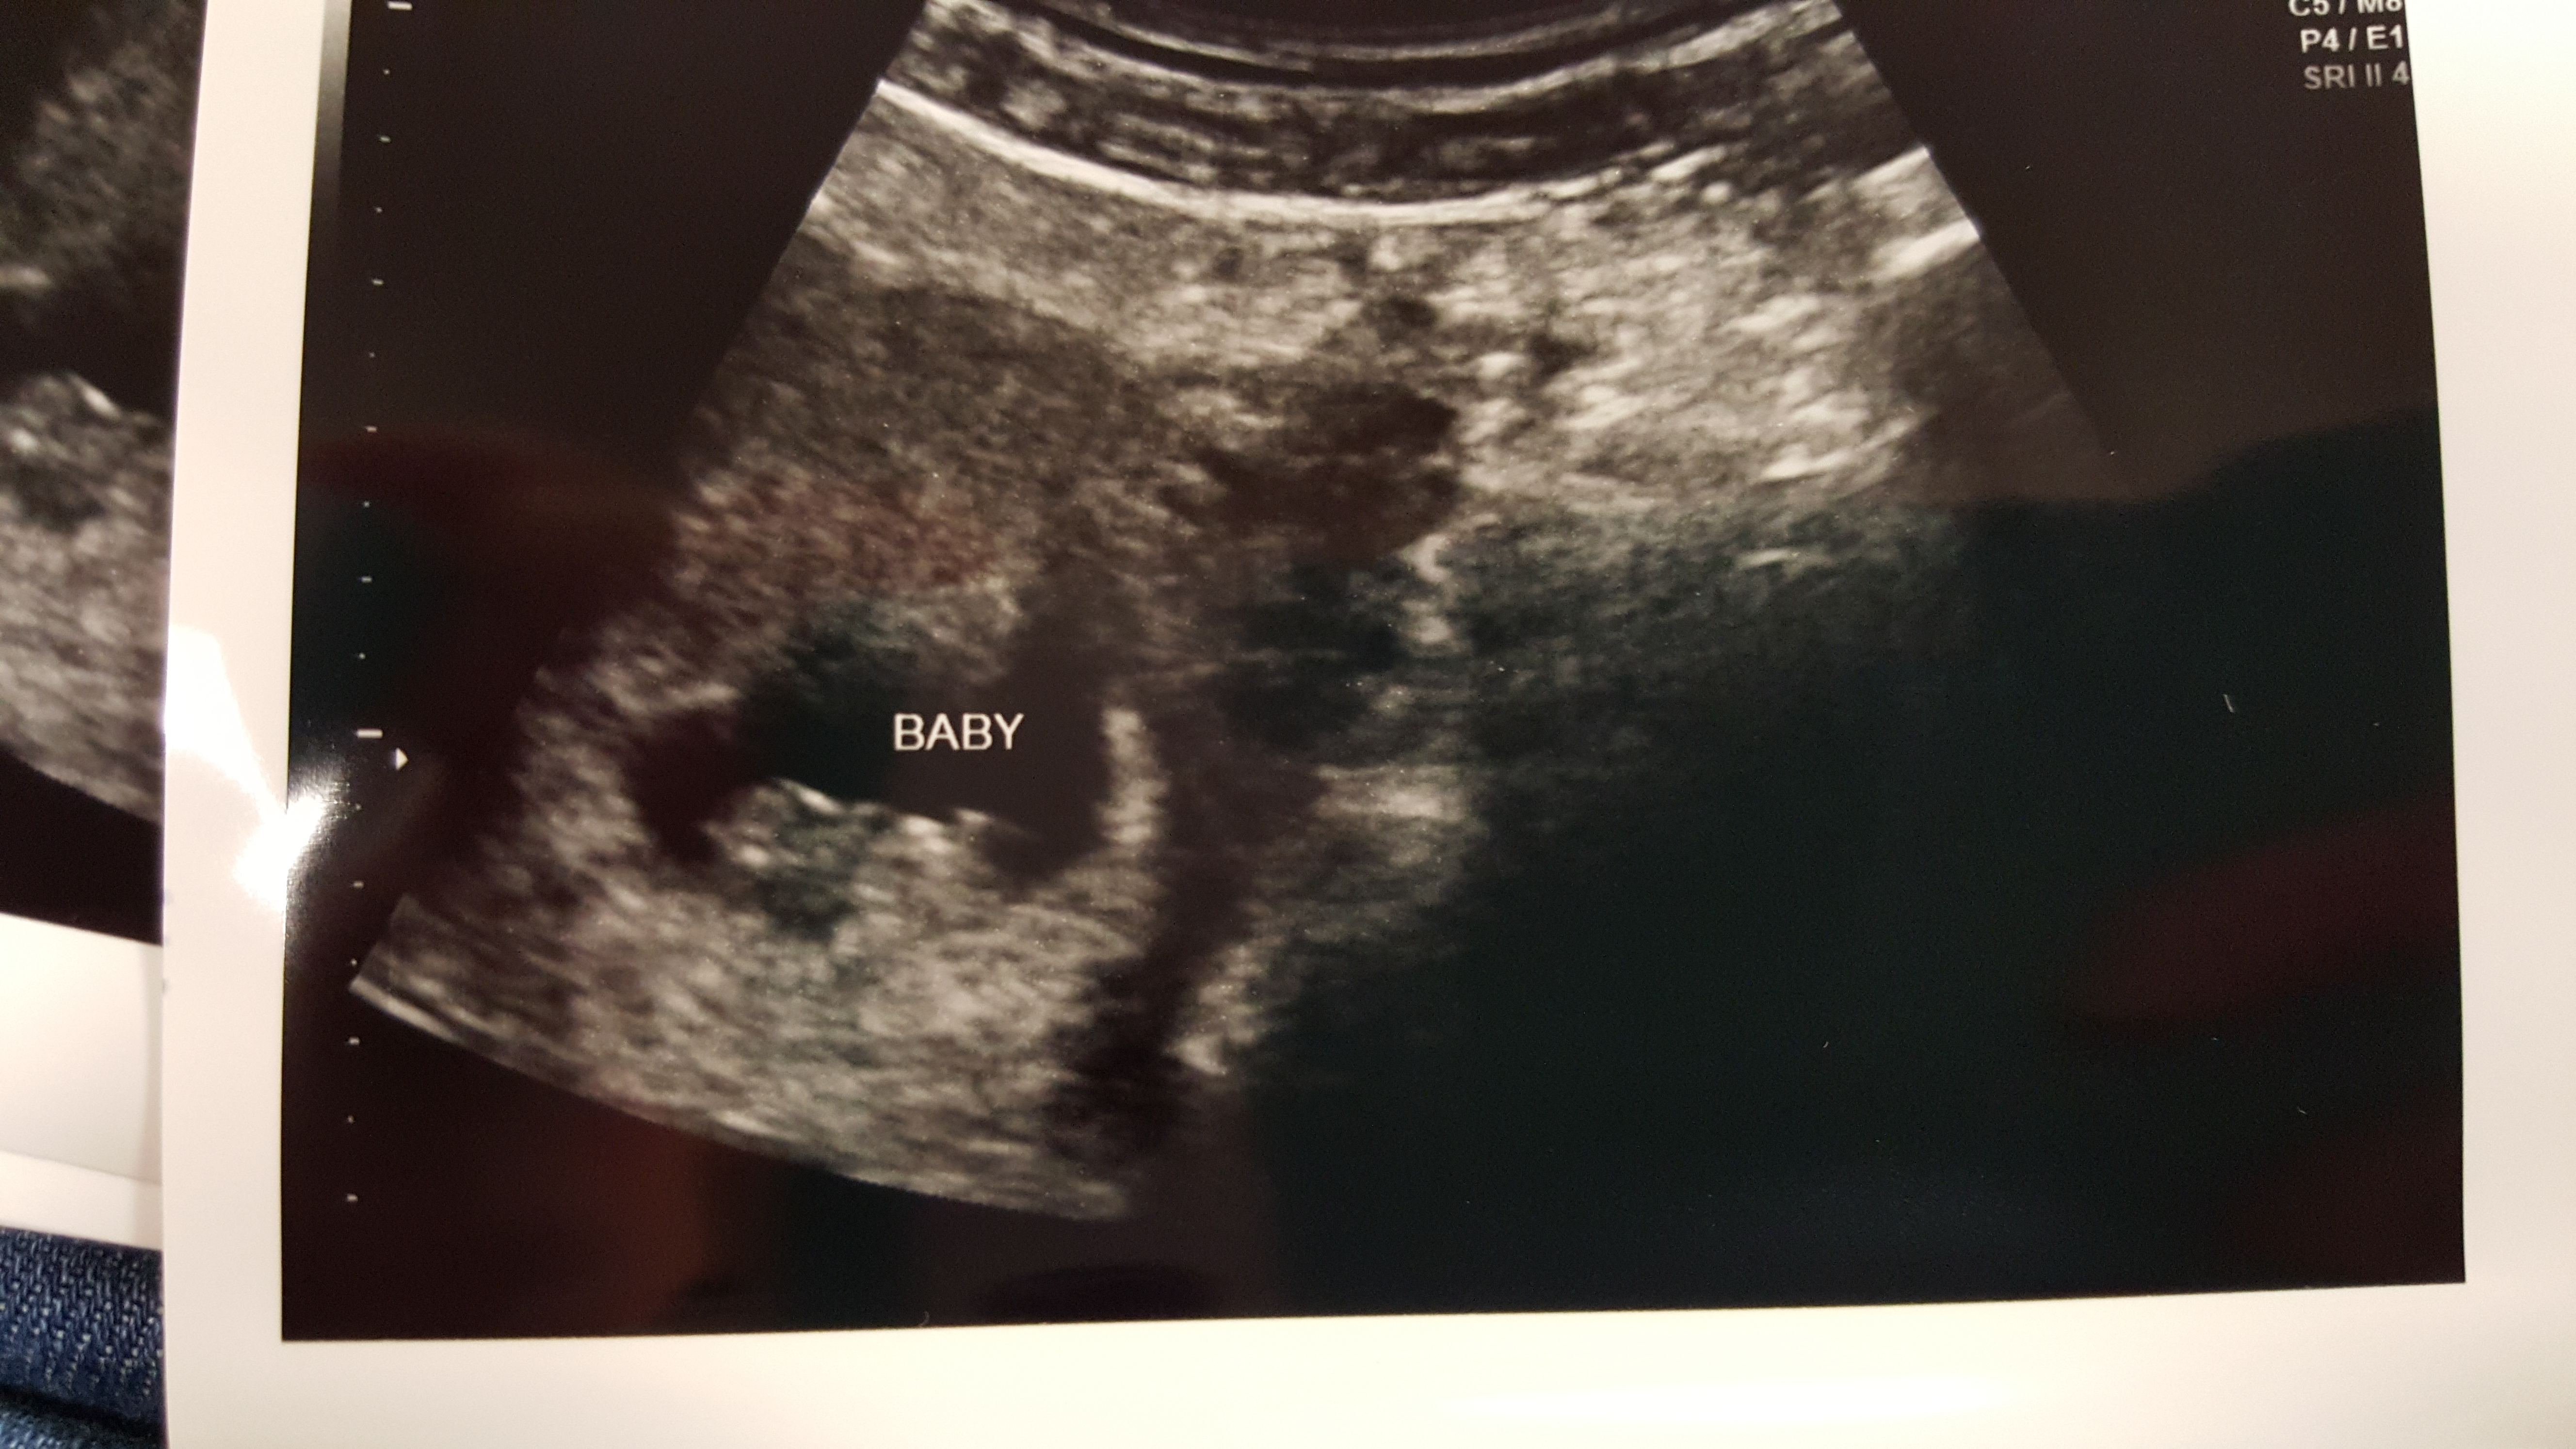

My first ultrasound pic at 9w3d. Measured a few days small. Doctor pointed out that I had twins, but one was not able to stick around We're sad about this, but we're thrilled to see our other healthy little baby! So in love!